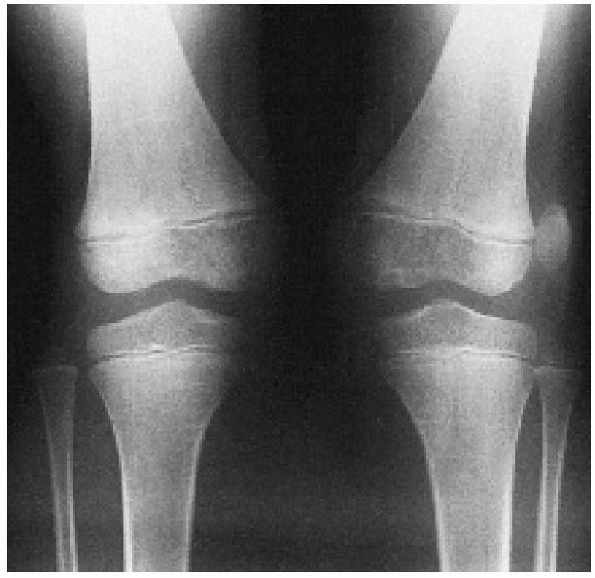

adolescents, especially girls. Several risk factors have been

identified in children likely to have chronic subluxation or

dislocation, including age younger than 16 years, radiographic evidence

of dysplasia of the patella or lateral femoral condyle, significant

atrophy of the vastus medialis obliquus, hypermobility of the patella,

and multiple previous dislocations (Fig. 24-21).